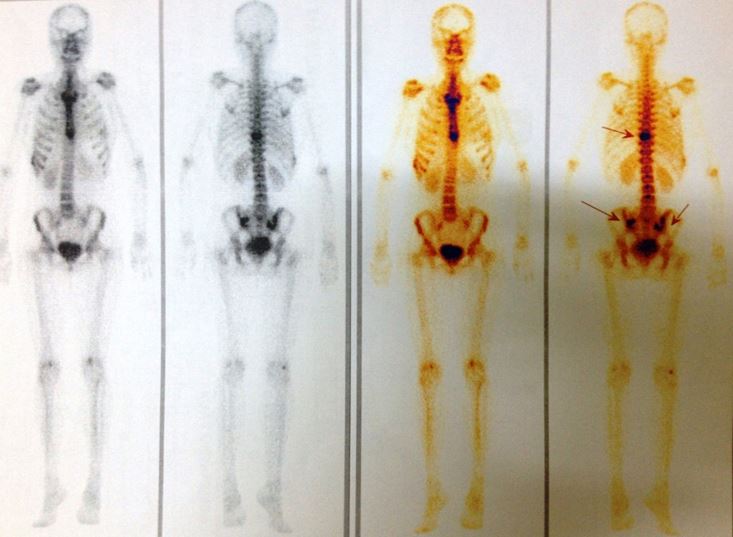

1. Xạ hình xương:

• Tăng hoạt độ phóng xạ tại đốt sống ngực 10, khớp cùng chậu hai bên (hình 5)

Hình 5: Trên xạ hình xương thấy hình ảnh tăng hoạt độ phóng xạ (đầu mũi tên) tại đốt sống ngực 10 và khớp cùng chậu hai bên.

1. Xạ hình xương (sau 5 tháng điều trị): Tăng hoạt độ phóng xạ tại đốt sống ngực số 10, cung trước xương sườn 9,10; xương chậu bên trái (đầu mũi tên hình 11)

Hình 11: Xuất hiện thêm tổn thương xương sườn trên xạ hình xương (bệnh nhân bị va đập vào vùng mạn sườn phải do tai nạn trước khi làm xét nghiệm xạ hình xương)

Xạ hình xương trước điều trị: tăng hoạt độ phóng xạ (đầu mũi tên) tại đốt sống ngực 10 và khớp cùng chậu hai bên

Xạ hình xương sau điều trị: Tăng hoạt độ phóng xạ tại đốt sống ngực số 10, cung trước xương sườn 9,10; xương chậu bên trái (đầu mũi tên hình 11).

Hình ảnh tăng hoạt độ phóng xạ tại cung trước xương sườn 9,10 tương ứng với vị trí va đập trước khi làm xạ hình xương (vòng tròn vàng).